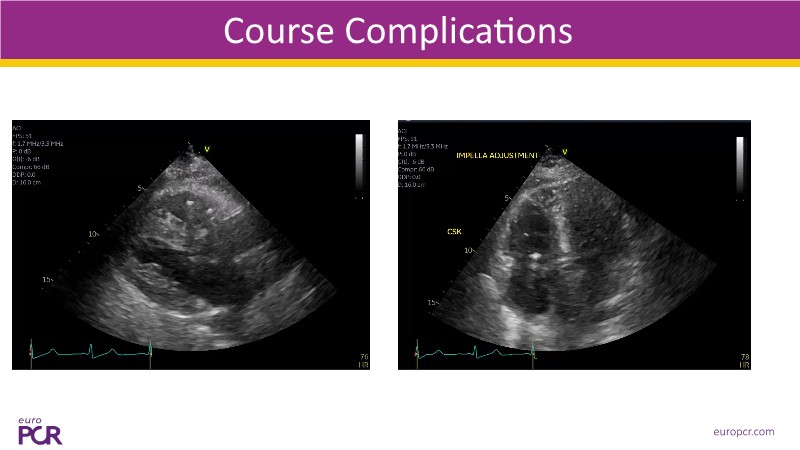

Explore how real-world data and evolving evidence are reshaping IV antithrombotic strategies in complex PCI. This EuroPCR 2025 session brings together urgent clinical cases—including STEMI patients in shock—and highlights key insights from the SMILE registry. Learn how transition protocols from cangrelor to oral P2Y12 inhibitors are applied in practice, compare approaches across Europe and the US, and get a forward-looking perspective on what’s next for IV therapies in 2025. A must-watch for anyone managing high-risk PCI.